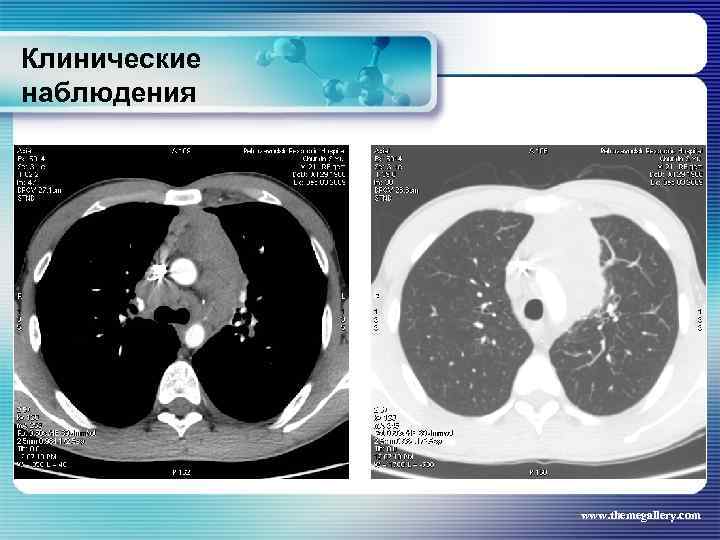

Клинические наблюдения Тот же пациент На основании выполненных исследований сформулирован клинический диагноз: лимфома Ходжкина, нодулярный склероз Grade II, III A E S стадия с поражением шейных, заднешейных, надключичных лимфатических узлов, средостения с прорастанием в левое легкое и плевру слева, внутригрудных лимфатических узлов, абдоминальных лимфатических узлов, селезенки. За время наблюдения проведено 8 циклов BEACOPP. На этом фоне достигнута в марте 2010 года парциальная ремиссия. При лучевом обследовании выявлена положительная динамика изменений. www. themegallery. com

Клинические наблюдения Тот же пациент На основании выполненных исследований сформулирован клинический диагноз: лимфома Ходжкина, нодулярный склероз Grade II, III A E S стадия с поражением шейных, заднешейных, надключичных лимфатических узлов, средостения с прорастанием в левое легкое и плевру слева, внутригрудных лимфатических узлов, абдоминальных лимфатических узлов, селезенки. За время наблюдения проведено 8 циклов BEACOPP. На этом фоне достигнута в марте 2010 года парциальная ремиссия. При лучевом обследовании выявлена положительная динамика изменений. www. themegallery. com

Клинические наблюдения www. themegallery. com

Клинические наблюдения www. themegallery. com

Клинические наблюдения www. themegallery. com

Клинические наблюдения www. themegallery. com

Клинические наблюдения www. themegallery. com

Клинические наблюдения www. themegallery. com

Клинические наблюдения www. themegallery. com

Клинические наблюдения www. themegallery. com

Клинические наблюдения www. themegallery. com

Клинические наблюдения www. themegallery. com

Клинические наблюдения Тот же пациент В июле 2010 года выполнена телегамматерапия на зоны первичной манифестации. Результаты лучевого обследования в настоящее время www. themegallery. com

Клинические наблюдения Тот же пациент В июле 2010 года выполнена телегамматерапия на зоны первичной манифестации. Результаты лучевого обследования в настоящее время www. themegallery. com